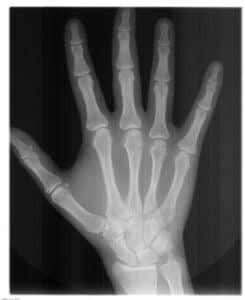

Das Handröntgen ist eine in der Kieferorthopädie früher weit verbreitete, heute obsolete Röntgenaufnahme der Hand. Kieferorthopäden glaubten lange Zeit, damit das zu erwartende, restliche Wachstum junger Patienten vorhersagen zu können. Neue wissenschaftliche Untersuchungen haben jedoch erwiesen, dass die Handröntgenaufnahme nicht geeignet ist, das Unterkieferwachstum oder das Körperwachstum genau vorherzusagen. Für die Planung kieferorthopädischer Behandlungen sind die Aussagen der Handröntgenaufnahme daher zu ungenau, so dass die Aufnahme ohne praktischen Wert ist.